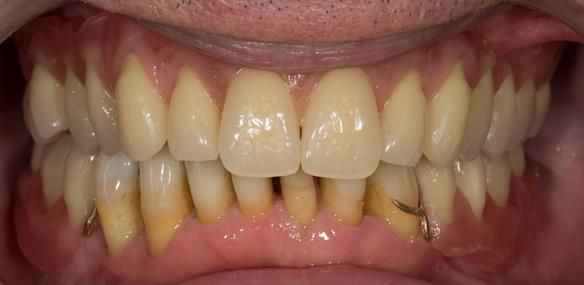

This 52 year old man was referred to me from his general dental practitioner in 2018.

10 years prior to consultation the patient's general dentist diagnosed periodontitis and referred him to Manchester Dental Hospital. He received a treatment plan to manage the periodontitis. Unfortunately, this was not acted on. Four years ago gaps developed between the upper front teeth. Orthodontic treatment was provided to align the teeth. A bonded retainer was fitted onto the upper front teeth. Approximately one year prior to consultation with me the patient noticed the teeth moving again. He consulted his orthodontist, who advised no further orthodontic treatment. One month prior to the consultation with me the upper left central incisor fell out whilst eating.

- Generalised periodontitis; stage IV grade C: currently unstable, risk factors: smoker.

- The remaining maxillary teeth had hopeless prognosis in the short term. They exhibited 80 - 100% alveolar bone loss with increased mobility (Grade 2 - 3).

- The lower right second premolar and lower left first premolar (LR5 LL4) had hopeless prognosis in the short term. They exhibited 80 - 100% alveolar bone loss with grade 3 mobility.

- The remaining mandibular teeth had approximately 30 - 50% alveolar bone loss with grade 1 mobility.